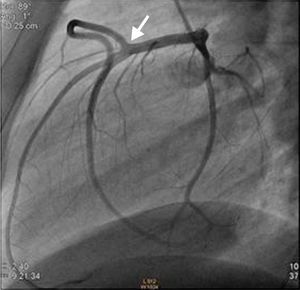

Caso clínicoDoente do sexo masculino de 22 anos de idade, raça caucasiana, fumador, consumidor esporádico de cocaína inalada e com história familiar de doença cardíaca isquémica. Foi admitido no serviço de urgência (SU) por clínica de dor precordial opressiva com 3 horas de evolução e que se tinha iniciado em repouso, cerca de 24 horas após o último consumo de cocaína. No SU ficou inicialmente assintomático após administração de nitrato sublingual. Encontrava-se hemodinamicamente estável (TA 123/67 mmhg; FC 92 bpm), sem sinais de hipervolemia, saturação de O2 de 97% por oximetria de pulso e apirético. O eletrocardiograma (ECG) da admissão não apresentava alterações de relevo. As análises mostraram elevação dos marcadores de necrose miocárdica com troponina i de 7 ng/ml, sem outras alterações. O ecocardiograma no SU mostrou hipocinesia das paredes posterior e inferior, com boa função global sistólica biventricular. No SU, apresentou recorrência de dor, tendo sido repetido eletrocardiograma que mostrou supradesnivelamento transitório de ST com 1mm nas derivações inferiores, tendo ficado assintomático e retornado ao padrão eletrocardiográfico inicial após nova administração de nitrato sublingual (Figuras 1 e 2).

Foi internado na unidade de cuidados intensivos coronários com diagnóstico de síndrome coronária aguda sem elevação do segmento ST e foi submetido a cateterismo urgente. A coronariografia excluiu doença aterosclerótica luminal, mas mostrou a presença de uma ACC. O doente apresentava um ostium coronário único em posição do Seio de Valsalva esquerdo, que originava o tronco comum. Este vaso apresentava um trajeto normal bifurcando-se numa artéria descendente anterior (DA) e numa artéria circunflexa com as distribuições anatómicas habituais. Por sua vez, a artéria coronária direita (CD) originava-se de forma anómala no segmento médio da DA e dirigia-se depois para a direita para vascularizar o seu território habitual. Para melhor definir as correlações anatómicas da coronária direita, realizou-se um AngioTC, que excluiu trajetos malignos deste vaso entre a aorta e a artéria pulmonar e documentou uma aparente escassez de suprimento arterial epicárdico nas paredes posterior e inferior, por ausência das artérias descendente posterior e póstero-lateral. O score de cálcio era 0.